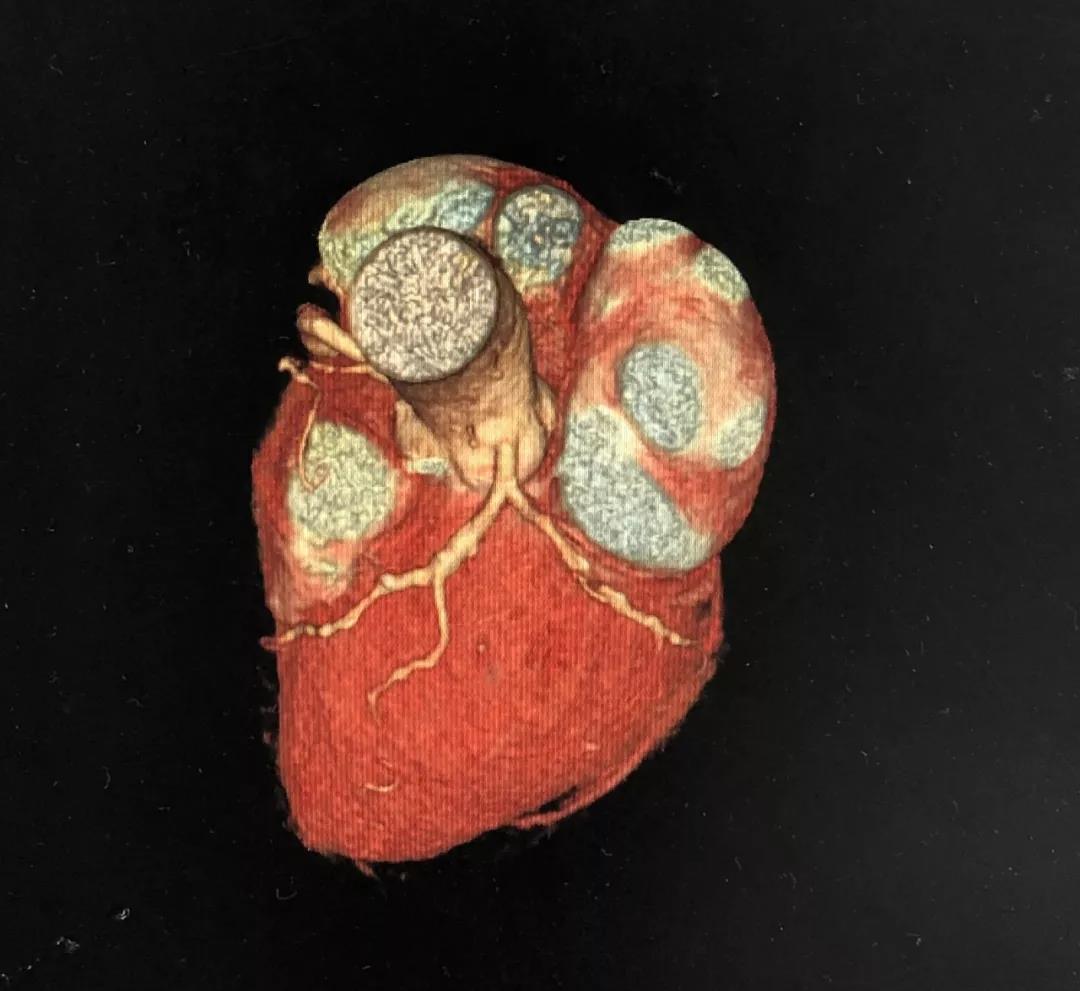

冠状动脉CTA

CCTA LAD病变特点:

近段血管较直

中远段血管偏细

中远段血管病变弥漫

病变段扭曲不很明显

病变段无重要分支发出

病变血管段有局灶点状钙化

CCTA LCX病变特点:

LM前分叉正常

LCX相对较直

中段病变伴局灶点状钙化

1、明确了LAD病变位于血管的中远段,比较弥漫,病变段血管整体偏细,是应用药物球囊的适应症;

2、根据CCTA检查的结果,知晓病变的情况,预先准备好相应型号的药物洗脱球囊;

3、病变段血管为局灶性钙化,提示病变的预处理应该会很顺利;

4、病变近段的血管较直,相对健康,药物球囊入路通畅;

5、左主干无钙化,前分叉正常,为选用7F指引导管和/或使用延长导管提供了机会。

一句话,CCTA提示LAD中远段的小血管病变,可以使用药物洗脱球囊处理(给术者吃了颗定心丸)。